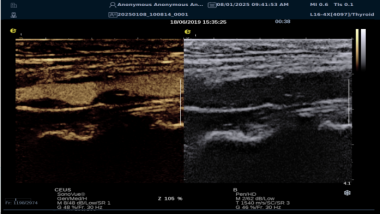

mFlowTM 超微血流显像技术

mFlowTM 超微血流技术在小型机器上率先实现微米级细小血管识别与低速血流捕捉,以往仅高端台式机具备此功能。该技术专注于颈动脉粥样硬化斑块内血流评估,无需造影剂,具有高分辨率、低运动伪像和高帧频成像特点。其优势如下:

image.png

? 运用 3D 壁滤波技术智能分析信号,可探测常规超声难以捕捉的低速血流,灵敏度高。

? 依据 Staub 标准对检查结果分级,直观展示斑块内新生血管血流,为斑块稳定性评估提供新指标。

? 基于多普勒原理,进行频谱测量并可进行VI指数测量,定量评估斑块内新生血管占比。

? 相较超声造影成像,无创便捷,为颈动脉易损斑块评估开辟新途径。

iPlane Vascular 平面波超微细血流显像技术

iPlane Vascular 技术借助 OmniSound?平面波和 3D 壁滤波技术突破,提升超声多普勒分辨率并具备定量测量能力。优势如下:

? 显著提高对低速血流的敏感度,实现高分辨率、高帧频实时微血流成像(分辨率 30 微米、帧频 150 /s),动态显示斑块内新生血管血流。

? 基于多普勒原理进行频谱测量与 VI 指数计算,定量评估斑块内新生血管。

? 成像质量接近造影效果且无需造影剂,无创简便,增强诊断准确性,适用于细微血流变化场景。